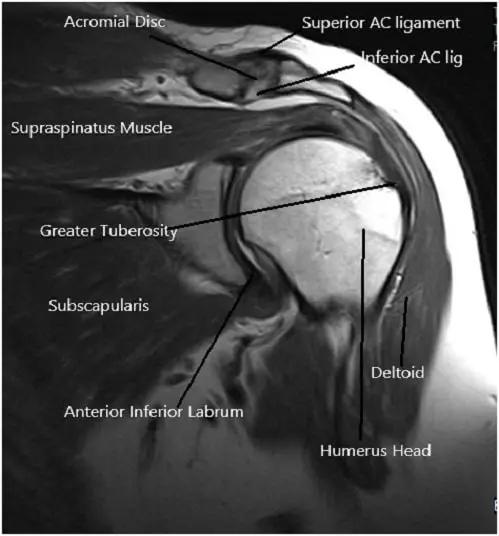

MRI of the left shoulder suggested tendinosis of the supraspinatus tendon with a partial articular surface tear of the anterior and mid substance fibers of the tendon. Tendinosis of the infraspinatus tendon. Subacromial/subdeltoid bursal fluid reflecting bursitis. Degeneration and tear of the anterosuperior labrum.

MRI image of the shoulder in axial and coronal sections